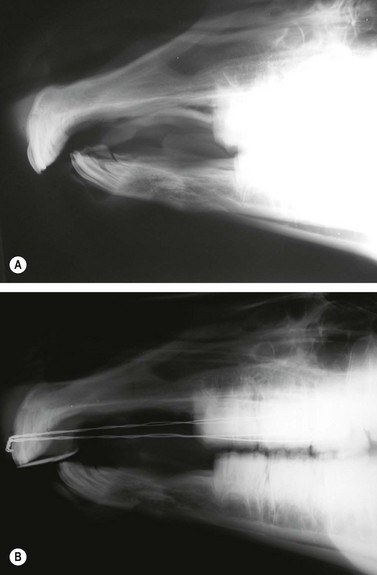

The most common indication for partial mandibulectomy is to remove a neoplastic lesion of the rostral aspect of the mandible. The most commonly encountered mandibular neoplasm is the juvenile ossifying fibroma, and this neoplasm is most commonly found on the mentum (Fig. 19.24). Consequently, the mentum is that portion of the mandible that is most frequently amputated. Other neoplasms sometimes encountered on the mentum include the carcinoma (Fig. 19.25) and ameloblastoma. Another indication for amputation of the rostral aspect of the mandible is fracture of the mentum not amenable to repair.

Fig. 19.25 Laterolateral radiograph of the skull of a horse with a carcinoma of the mandible. The rostral portion of the mandible of this horse was amputated caudal to the symphysis.

The mandible is transected caudal to the lesion but rostral to the caudal margin of the symphysis using an oscillating saw or obstetrical wire (Figs 19.26 & 19.27). If necessary, hemorrhage from the mandibular stump can be ameliorated by applying bone wax to the cut edge of the bone. Sharp edges of bone are smoothed with a rongeur. The submucosa and periosteum of the lingual flap are apposed to the submucosa and periosteum of the labial flap, using 2-0 or 0-absorbable suture in a simple-continuous or cruciate suture pattern, and the mucosal margins of the flaps are apposed with simple-interrupted, cruciate, or vertical mattress sutures using the same suture material (Fig. 19.28). Inserting a Penrose drain into the space between the two flaps through a stab incision created on the ventral aspect of the mentum prevents formation of a hematoma between the two flaps. Phenylbutazone should be administered twice daily for at least several days after surgery to provide analgesia.

image

Fig. 19.26 The mandible is transected caudal to the lesion but rostral to the caudal margin of the symphysis using an oscillating saw or obstetrical wire.

Fig. 19.27 Transected portion of the jaw containing a juvenile, ossifying fibroma.